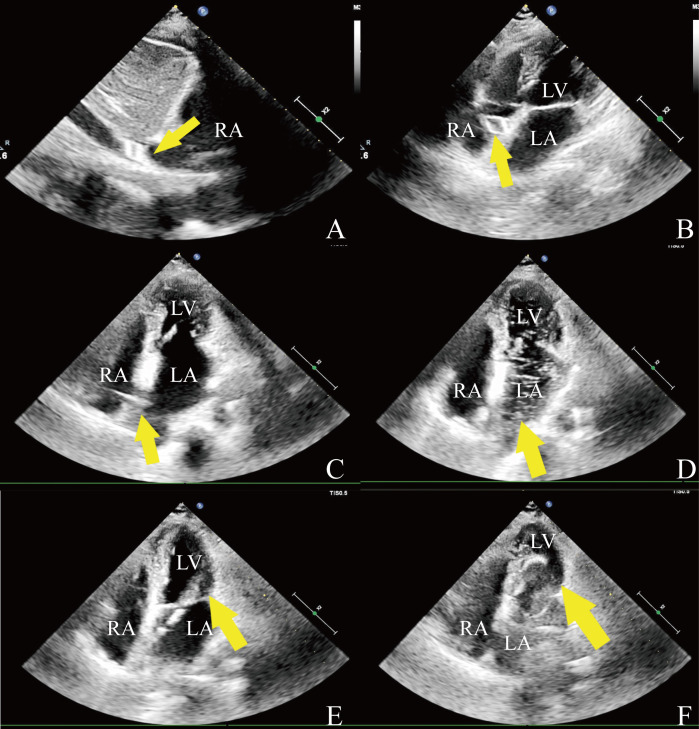

Abstract Image